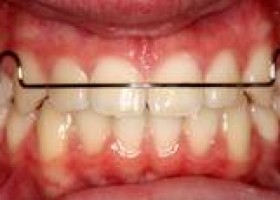

Traditional metal braces are the most common type of braces and are more comfortable today than ever before. Made of high-grade stainless steel, metal braces straighten your teeth using metal brackets and archwires. With metal braces, you have the option of adding colored elastics (rubber bands) for a more unique and colorful smile.

Ceramic braces are made of clear materials and are therefore less visible on your teeth than metal braces. For this reason, ceramic braces are used mainly on older teenagers and adult patients who have cosmetic concerns. While they are visually less prominent, they do require more attention to oral hygiene as ceramic braces are larger and are more brittle than their metal counterparts. For these reasons, ceramic braces tend to be used more on upper front teeth than on lower teeth.

Invisalign is a proprietary method of orthodontic treatment which uses a series of clear, removable teeth aligners used as an alternative to traditional metal dental braces. Invisalign gives you straight teeth without using braces.

Lingual braces custom made fixed braces. In lingual braces the brackets are cemented onto the backside of the teeth making them invisible. Hence, Lingual braces are a cosmetic alternative to those who do not wish the braces to be visible. Lingual Braces are commonly used to fix Bad bite occurring as a result of misaligned teeth. Also used to correct Gaps, crowding, rotated teeth, hence improving the cosmetic appearance of the teeth.

In conventional orthodontic treatment anchorage support usually taken from posterior teeth. In implant supported orthodontic treatment anchorage is taken from mini implants, which are inserted into the bone with minor surgical procedure. This technique can provide absolute anchorage, so that it can provide better aesthetic results.